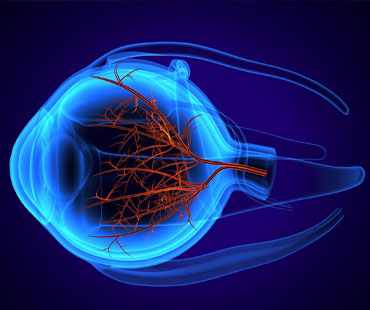

IDR EYE CARE is an eye care facility provider. We specialise in all kind of Cataract, glaucoma, retinal diseases, paediatric ophthalmology, refractive surgeries and more.